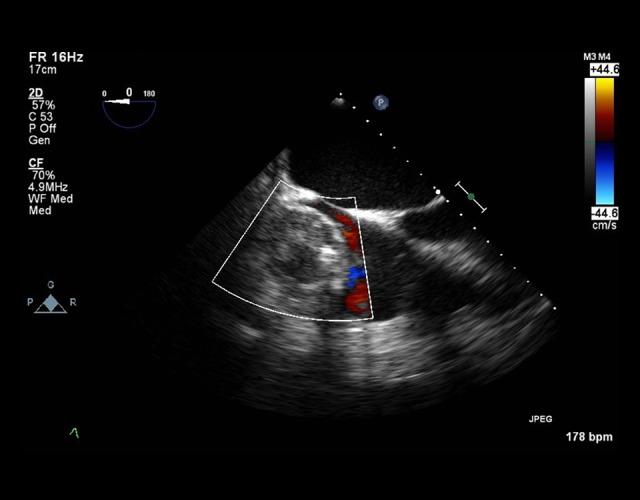

BACKGROUND Intracardiac abscesses are an unusual occurrence in developed countries. With the increase in use of implantable cardiac devices, the increase use of and advancements in antibiotics, and the longevity of patients with cardiac devices, one may expect an increase in such infections; however, case reports are rare. We are presenting a case in which hematogenous dissemination of methicillin-sensitive Staphylococcus aureus (MSSA) infection from a lower extremity diabetic ulcer propagated into an infected pacemaker lead and ultimately an intracardiac abscess of the right atrium. CASE REPORT A 77-year-old male with a history of MSSA diabetic foot infection complicated by osteomyelitis presented with fever, syncope, and wide complex tachycardia, and he was found to have an intracardiac abscess and fibrinous lead vegetations. The patient was deemed too ill for invasive surgical intervention given his comorbidities, pacemaker generator replacement requirement, and intermittent ventricular tachycardia. The patient was subsequently sent home with oral antibiotics and home hospice per patient and family wishes. CONCLUSIONS This case demonstrated how hematogenous dissemination of MSSA infections from a diabetic foot ulcer and osteomyelitis can seed pacemaker hardware resulting in an intracardiac abscess. Unfortunately, our patient was too ill to undergo all procedures required to eradicate the abscess and infected pacemaker hardware. The standard of care would be complete hardware removal. Conservative management would include indefinite or prolonged antibiotic therapy, with the notion that intracardiac abscesses cannot be cured with antibiotics alone. This conservative management approach would be deemed necessary in a select population that cannot undergo surgical intervention.

一名77岁男性,有MSSA糖尿病足感染合并骨髓炎病史,出现发热、晕厥和宽QRS波心动过速,被发现有心内脓肿和纤维蛋白性导线赘生物。鉴于其合并症、需要更换起搏器发生器以及间歇性室性心动过速,该患者被认为病情过重,无法进行侵入性手术干预。随后,根据患者及其家属的意愿,患者口服抗生素并接受家庭临终关怀后出院。